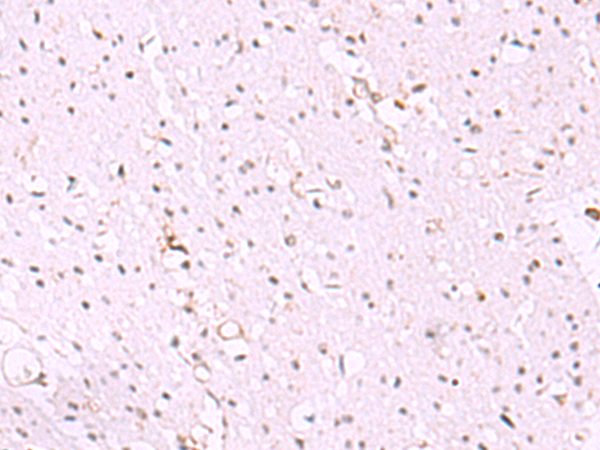

分类: 科研抗体货号: P13569别名: HEXO; THEX1; 3'HEXO应用: IHC反应种属: Human, Mouse, Rat

分类: 科研抗体货号: P13570别名: B7y; B7H7; B7-H5; B7-H7应用: IHC反应种属: Human

分类: 科研抗体货号: P13586别名: ABBP1; HNRPAB应用: WB,IHC反应种属: Human, Mouse

分类: 科研抗体货号: P13568别名:应用: WB,IHC反应种属: Human

分类: 科研抗体货号: P13585别名: FBRNP; HNRPA3; D10S102; 2610510D13Rik应用: WB,IHC反应种属: Human, Mouse, Rat

分类: 科研抗体货号: P13567别名: Mgn; HESL; HCM1228; bHLHb44应用: WB,IHC反应种属: Human, Mouse

分类: 科研抗体货号: P13583别名: HNF6; HNF-6; HNF6A应用: WB,IHC反应种属: Human, Mouse, Rat

分类: 科研抗体货号: P13566别名:应用: IHC反应种属: Human, Mouse

分类: 科研抗体货号: P13592别名: HOX4; HOX4B; HHO.C13; HOX-5.1; Hox-4.2应用: IHC反应种属: Human, Mouse

分类: 科研抗体货号: P13582别名: TCF; HNF4; MODY; FRTS4; MODY1; NR2A1; TCF14; HNF4a7; HNF4a8; HNF4a9; NR2A21; HNF4alpha应用: IHC反应种属: Human, Mouse, Rat